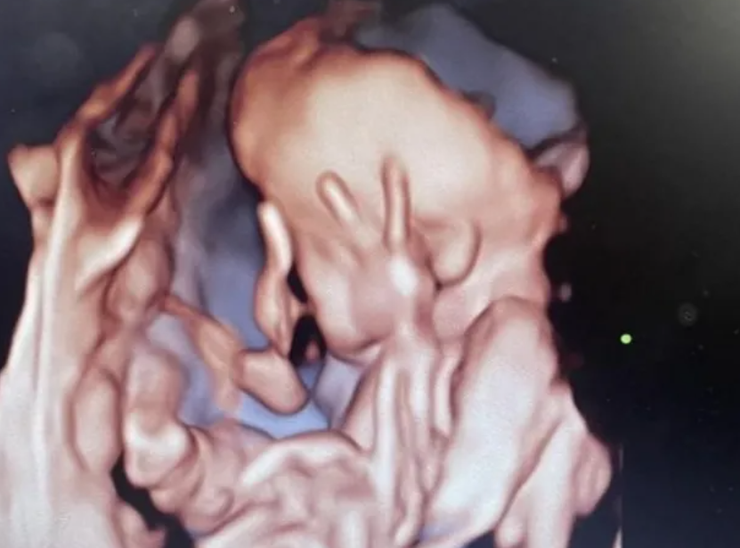

Чтобы окончательно убедиться, что рисков для жизни и здоровья нет, британка обратилась в частную клинику. Ее удивлению не было предела, когда во время очередного УЗИ малышка выставил пальчики вверх, как будто отмахиваясь от матери, которая не дает ей покоя.

"Она сначала не смотрела в камеру, а потом через несколько секунд уже поднимала пальцы вверх, будто сказала: "Я в порядке — уходи", — вспоминает тот курьезный инцидент мать.

Бабушка Кэти также шутит: "Точно будет наглой, когда родится и подрастет".

Увиденное на УЗИ рассмешило мать